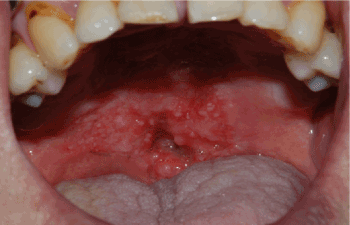

Figure 1. Pre-radiotherapy state of soft palate cancer in 69-year old male patient